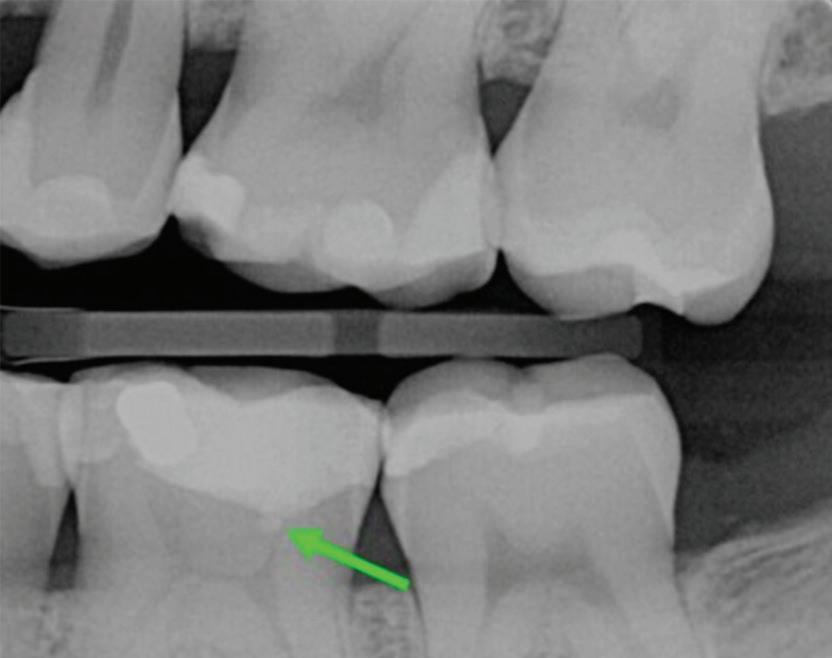

Fig 1. Proximity of root apices to vital structures. A. The periapical radiograph indicates that the apices of the mandibular right second molar and second premolar are in proximity to the inferior alveolar and mental nerves. B. A coronal CBCT image more clearly demonstrates the proximity of the molar apex to the inferior alveolar nerve. C. A coronal CBCT image more clearly demonstrates the proximity of the premolar apex to the mental nerve.

The inferior alveolar canal courses closely beneath the apices of mandibular molars, particularly second molars. Studies have shown that in more than 25% to 30% of patients, the inferior alveolar canal lies within 1 mm of the root apices of second molars; the prevalence is even higher in female and older patients due to reduced bone volume (Fig 1).8

Fig 2. Calcium hydroxide extrusion. During treatment of the mandibular left first molar, dysesthesia (burning pain) and paresthesia resulted from a substantial overfill of calcium hydroxide into the inferior alveolar nerve canal. (Courtesy of

radiographic findings, or an apical resorption, a fenestration, or an anatomical anomaly is suspected, reliance on periapical radiographs alone may result in missed diagnoses or mismanagement (Fig 4).